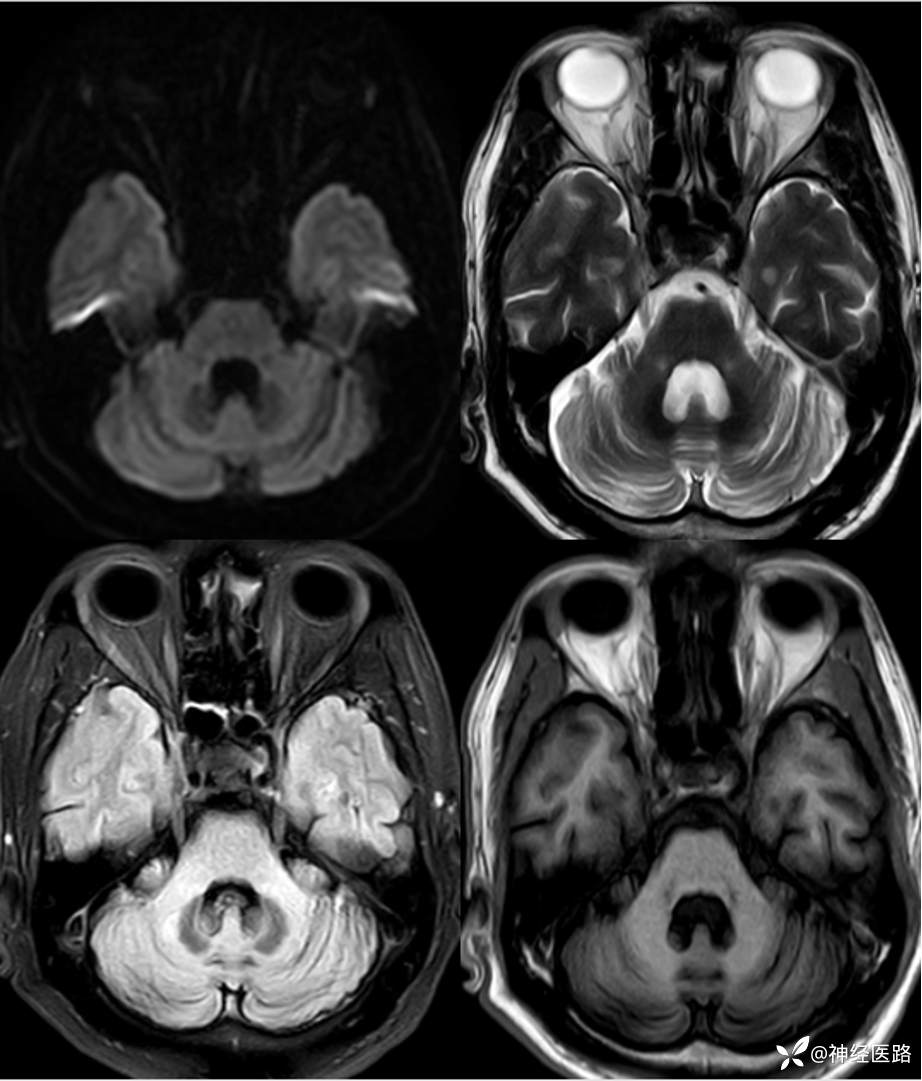

辅助检查:头部磁共振:1.颅脑DWI未见明显异常扩散受限。 2.脑白质高信号,脑萎缩。3.双侧上颌窦、双侧筛窦、双侧额窦炎。

两次影像对比